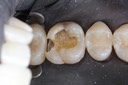

Alan Chinn #28 caries removal

Alan Chinn #28 prep

Alan Chinn #28 finish